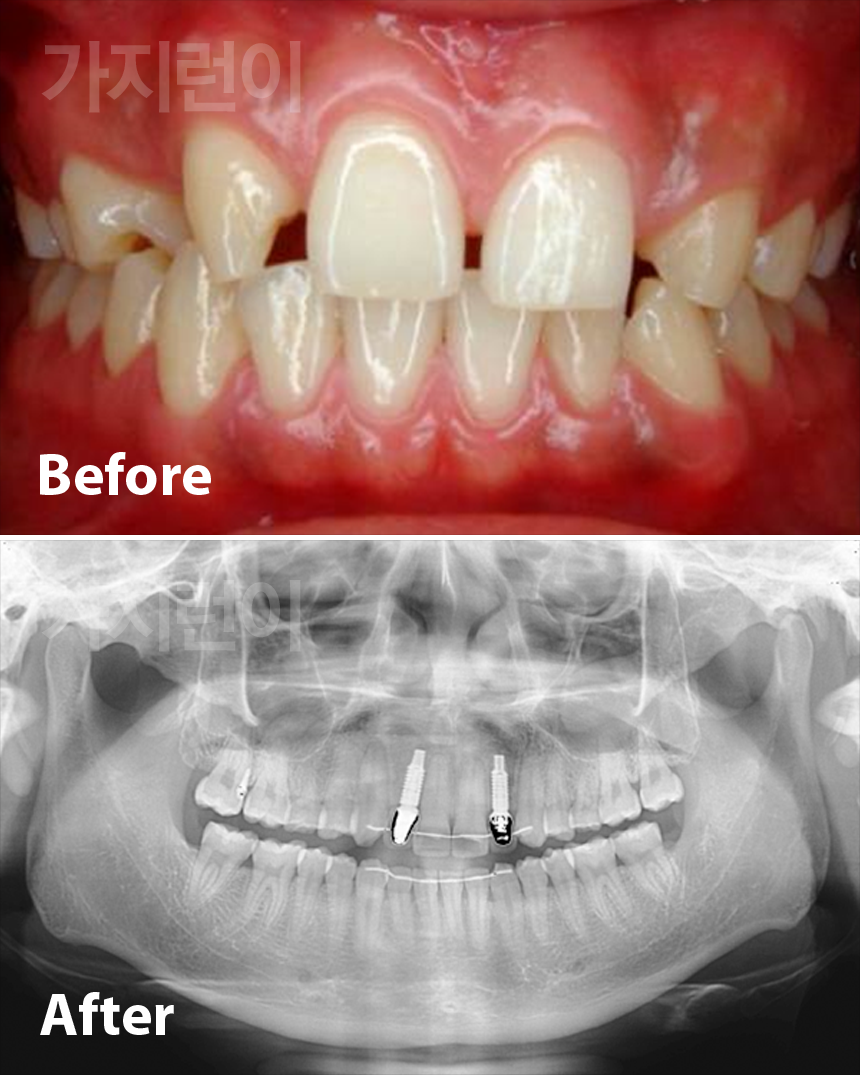

• 선천적 결손치아의 임플란트 공간마련